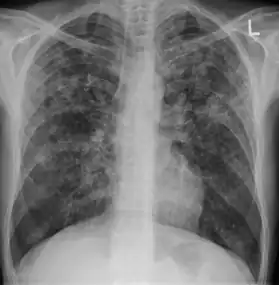

| Chest X ray showing miliary tuberculosis | |

Miliary tuberculosis is a form of tuberculosis that is characterized by a wide dissemination into the human body and by the tiny size of the lesions (1–5 mm). Its name comes from a distinctive pattern seen on a chest radiograph of many tiny spots distributed throughout the lung fields with the appearance similar to millet seeds—thus the term "miliary" tuberculosis. Miliary TB may infect any number of organs, including the lungs, liver, and spleen.[2] Miliary tuberculosis is present in about 2% of all reported cases of tuberculosis and accounts for up to 20% of all extra-pulmonary tuberculosis cases.[3]